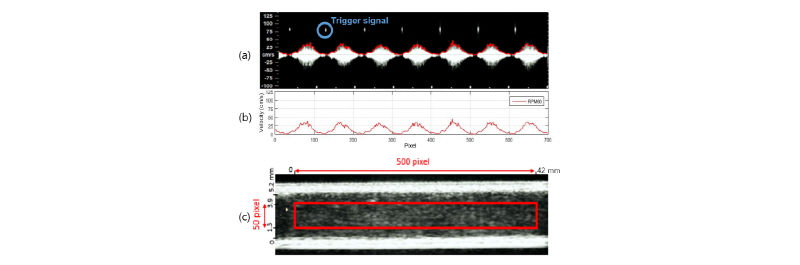

Fig. 4.

(a) Spectral Doppler waveform at 60 r/min with 5 MHz trigger signals. (b) Extracted blood flow velocity for image processing. (c) Ultrasound B-mode image and the window for averaging of echogenicity over 500 pixel x 50 pixel for temporal variation during a cycle. The fluid used in this ultrasound images is porcine blood.

초음파 영상 시스템을 이용하여 1 s에 28 프레임 씩 펌프 5주기 동안의 도플러, B-모드 영상을 수집하였다. 수집한 5 주기의 도플러 소노그램을 영상처리를 하여 혈류 속도의 변화를 추출 하였다. 관심 지역을 설정 한 뒤에 경계 값을 설정하여 혈류속도의 최고점들의 좌표를 추출하였고 펌프 주기의 시작점마다 들어오는 트리거 신호를 필터를 씌워 제거 하였다[Fig. 4(b)].

시간에 따라 변하는 에코 정보를 추출하기 위해 B-모드 영상에서 임의의 면적을 설정하여 평균하였고 그 면적은 Fig. 4(c)에 빨간색의 사각형으로 나타내었다. 가로축은 500 픽셀(pixel)이고 그에 해당하는 실제 길이는 52 mm이다. 세로축은 50 픽셀로 그에 해당하는 길이는 2.6 mm이며 총 혈관 내경의 1/4이 되는 1.3 mm 지점과 3/4이 되는 3.9 mm 지점을 기준으로 잡았다. 면적의 평균값을 시간축의 그래프로 나타내었다.

혈관벽의 움직임은 Fig. 4(c) B-모드 영상의 세로축 한 라인에서 시간에 따라 변하는 혈관벽의 움직임을 측정 하였다. 동맥벽의 확장은 Fig. 4(c)의 B-모드 영상으로부터 측정하였다. B-모드 영상의 픽셀과 실제 길이의 비는 세로 1/0.052, 가로 1/0.084(pixel/mm)이며 단위를 길이로 맞추었다. 시간축과 세로축의 한 프레임의 영상으로 변환한 뒤 경계선 검출법을 이용하여 다섯 주기 동안의 혈관벽 움직임을 측정하였다.